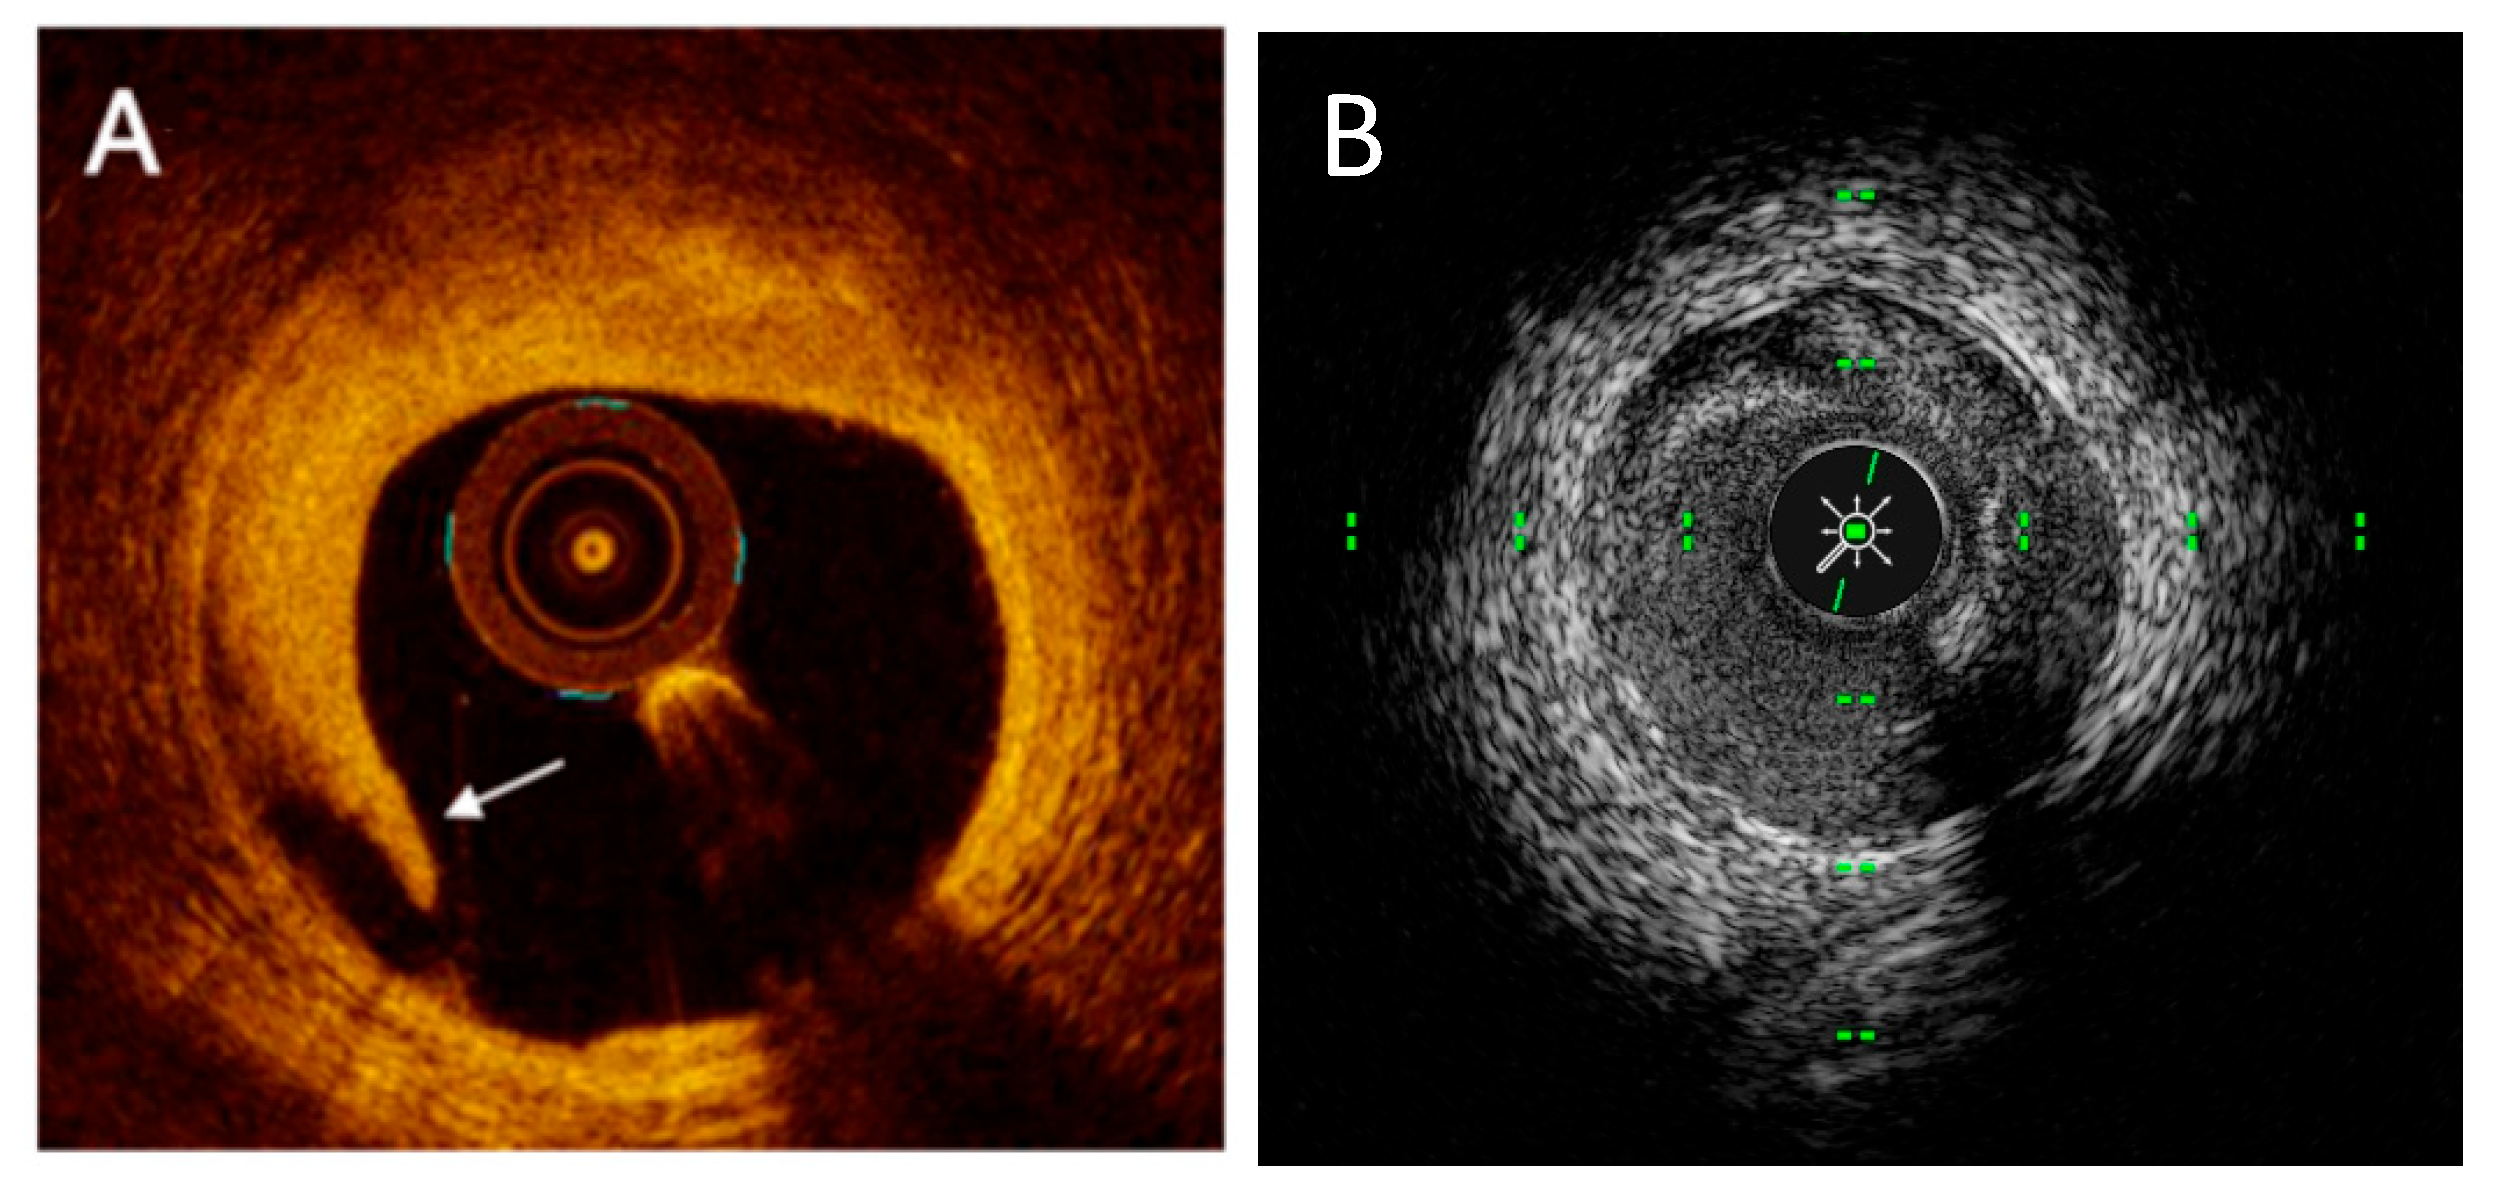

2.2. OCT Technology